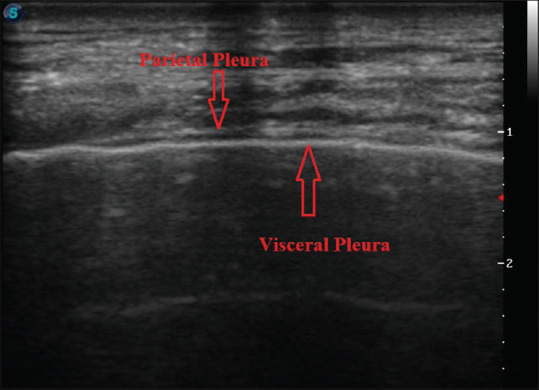

Methods: The files of patients who underwent thoracic USI and thoracentesis due to PF accumulation were retrospectively examined. PF sonographic patterns and pleural thicknesses were retrieved from the USI records. Based on the Light's criteria, PFs were classified into transudative PF (TPF) and exudative PF (EPF). A scoring system was established based on the sonographic patterns and pleural thickness. Sonographic scores and other clinical, radiological, and demographic characteristics of the two groups were comparatively analyzed.

Results: Among the 64 cases analyzed, 32 (50%) were categorized as TPF. The average pleural thickness in the TPF group was 1.4 mm. The hypoechoic sonographic pattern rate in the TPF group (75%) was significantly different from that in the EPF group (p < 0.001). A hypoechoic sonographic pattern (p = 0.002) and pleural thickness >1.5 mm (p = 0.031) were independent predictors of EPF. The scoring system demonstrated a sensitivity of 84.38% and a specificity of 75.00% for predicting EPF when the sonographic score was ≥3.

Conclusion: Thoracic USI can serve as a noninvasive method to predict the nature of PFs by combining sonographic patterns and pleural thickness.